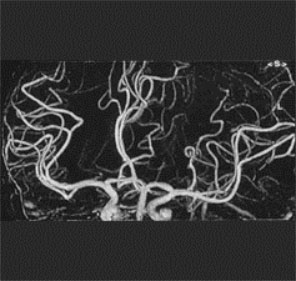

血管造影(アンギオグラフィ)

血管造影検査(アンギオ検査)とは、カテーテルといわれる細い管を主に鼠けい部の動脈から穿刺し、目的の部位(肝臓・骨盤)まで 透視画像を見ながら挿入していきます。挿入したカテーテルから造影剤を注入し、血管の走行や狭窄、腫瘍の染まり方を知るための検査です。

主にインターベンショナル・ラジオロジー(IVR)と呼ばれる血管内治療に使用されています。

12×16インチの大視野FPDを搭載し、頭部・腹部・つま先まで全身の血管をカバーし、多目的に検査可能です。

また低線量(被ばくを減らし)ながらもきれいな画像が表示・撮影できます。

LCI(Low Contrast Imaging)と呼ばれるCTのような画像が撮影できます。